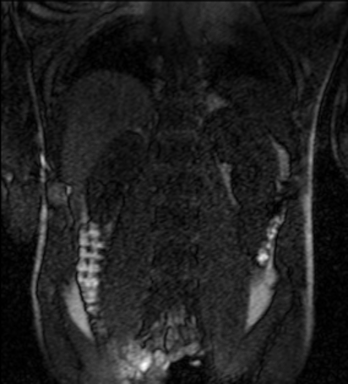

Tables 1 and 2 show our quantitative results: PSNR between the style (image we want to transfer style from) and generated image, SSIM and MS-SSIM between the content (image we want to take structure from) and generated image and finally, our proposed weighted SSIMs. For each style transfer direction and metric, our method consistently outperforms the other approaches. Figures 2 and 3 qualitatively highlight the good results of our method on 2D and 3D datasets. In addition, quantitative results on both figures show that our proposed metric preserves qualitative ordering of results for both style and content. In comparison, metrics such as SSIM struggle to accurately correlate to visual results.

Qualitative evaluation shows that the proposed method leads to sharper images, better content preservation, better localised CE and realistic MRI appearance. Quantitatively, we outperform the other algorithms with each metric, for each style transfer direction. While we expected that adding CE to images would be an easier task than removing CE, we found that for both tasks the method exhibits similarly performing quantitative and qualitative results. The results for style transfer with the kidney data show that when there is clear CE, it is easier to perform style transfer in both directions. However, when style transfer is performed on the prostate data, the model struggles in comparison to the kidney data. This may be due to the enhancement of the prostate being less defined than the kidney data. In figure 3(b), we can see the prostate with CE. Compared to figure 2(b) showing kidneys with CE, it is harder to determine the edges. The two original images shown in figures 3(a) and 3(b) are clear and easy to see some edges of prostate, in other images, it is harder to see the edges of the prostate.

(C) CW-SSIM: 0.61

(S) CW-SSIM: 0.52

(C) CW-SSIM: 0.42

(S) CW-SSIM: 0.19

(C) CW-SSIM: 0.28

(S) CW-SSIM: 0.49

(C) CW-SSIM: 0.92

(S) CW-SSIM: 0.59